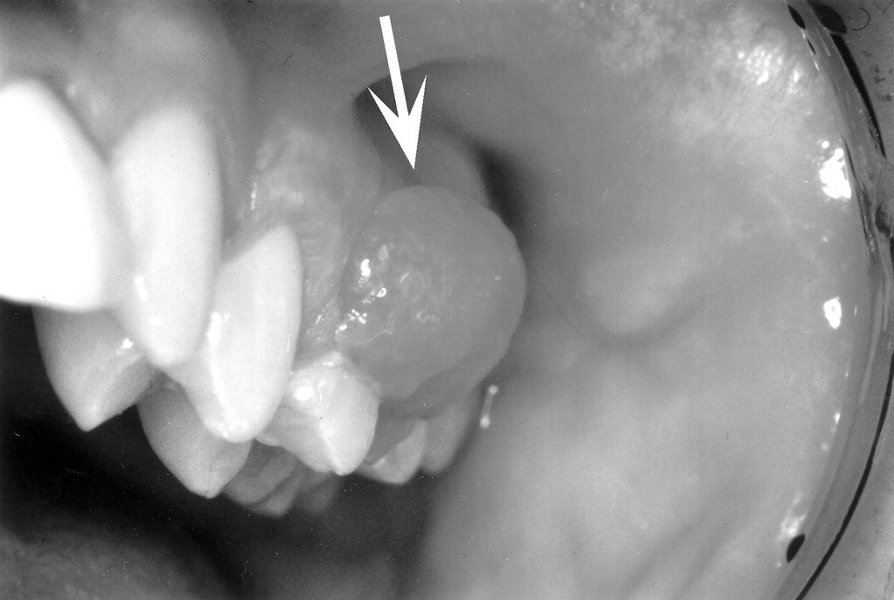

EPULIS gornje čeljusti u području pretkutnjaka i kutnjaka

epulis (epi- + grč. οὖλον: désni), tumoru slična dobroćudna tvorba izazvana lokalnim podražajem koja nastaje na desnima. Može narasti do nekoliko cm. S desnima je obično srasla uskom peteljkastom bazom, a rijetko širokom. Različiti patološki procesi mogu se klinički pojaviti kao epulide. Neonatalni ili kongenitalni epulis benigna je peteljkasta tvorba na desnima novorođenčeta u prednjem dijelu gornje ili donje čeljusti, režnjasta izgleda, ružičaste boje i veličine do nekoliko centimetara; može zadavati teškoće pri hranjenju, a liječi se kirurški. Piogeni granulom mekana je, crvena i ulcerirana tvorba na gingivi građena od granulacijskoga tkiva. Epulis orijaških stanica ili periferni gigantocelularni granulom najčešće se nalazi u mladih žena na donjoj čeljusti. Površina mu je glatka ili režnjasta, građa čvrsta ili spužvasta, a boja ružičasta do purpurno-plava. Smješten je na desnima u prednjem dijelu predvorja usne šupljine gornje ili donje čeljusti i obično prekriva više zuba. Epulide se kirurški liječe izrezivanjem (ekscizijom).